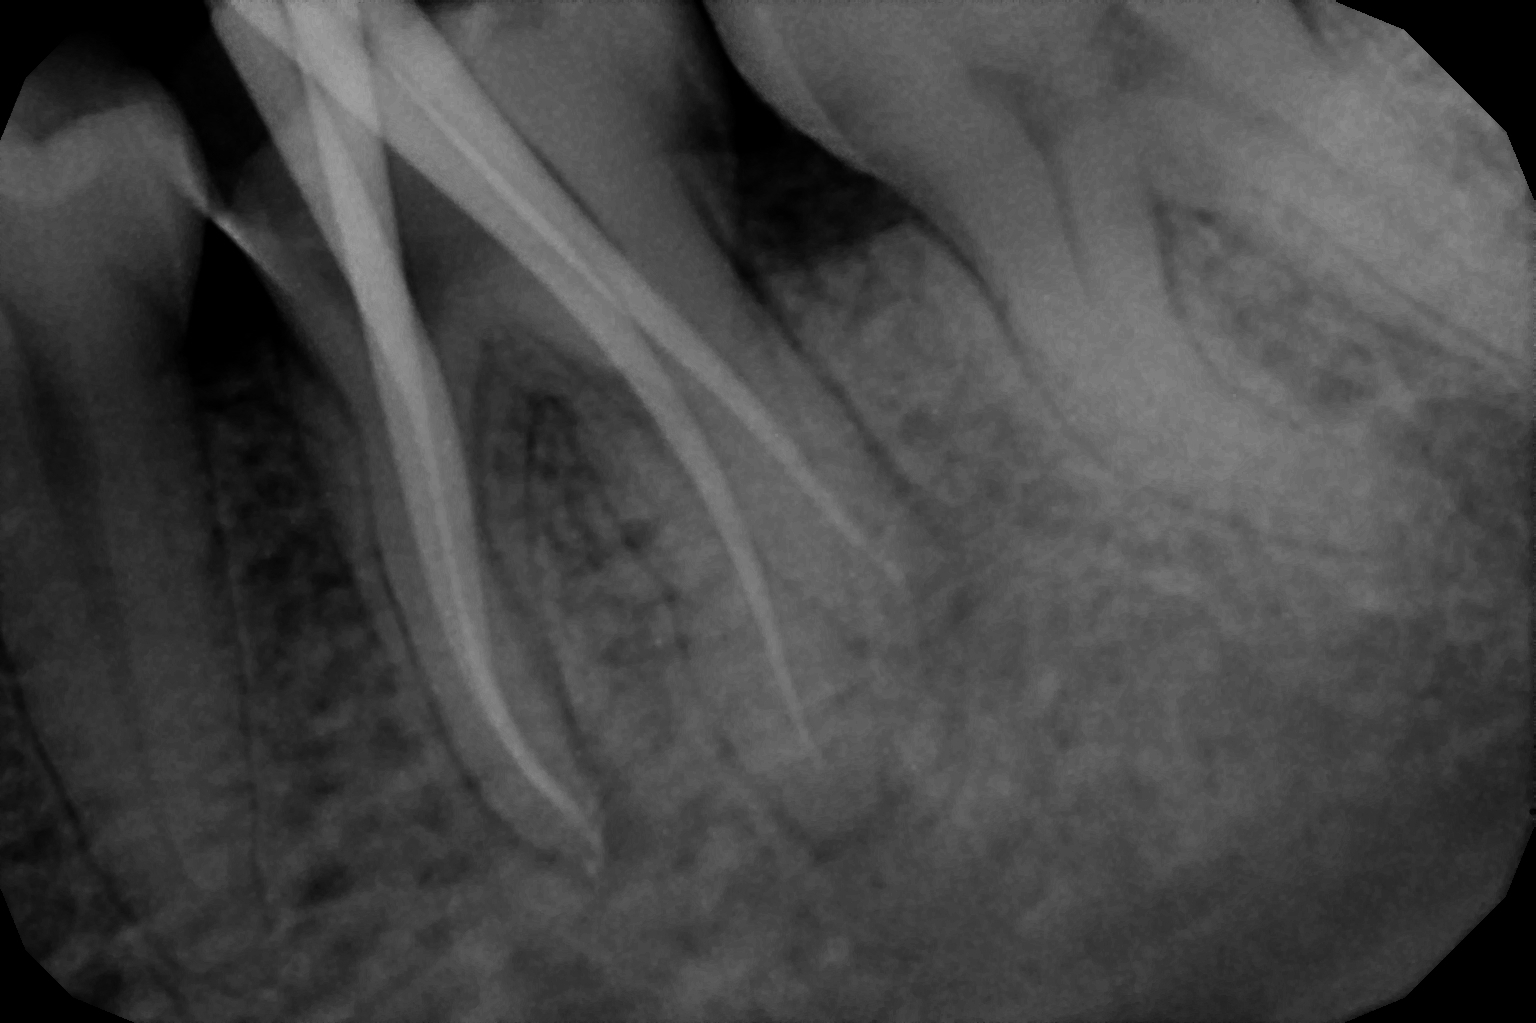

When the tooth is is sensitive to particularly hot and cold. When you cannot chew from that side or there is associated action of pain and swelling with same tooth, root canal treatment can save the tooth. For root canal treatment our clinic is equipped with state-of-the-art facility. We are following the protocol that is universally accepted and considered as a gold standard We are using rubber Dam for maximum possible cases. The root canal treatment is done under local anaesthesia that's why mostly it is painless . The rubber Dam isolation helps in proper irrigation and it provides much needed ease to the operating dental surgeon and the patient . The sealer and filling material are one of the Prime requisite of quality root canal treatment, it needs use of multiple X rays to really judge whether the results are acceptable or not. In older days root canal was just about cleaning the decade portion, removing the Pulp and filling it with biocompatible material but nowadays the root canal treatment it is very much advanced the precision is increased manifold. The materials and armamentarium that is required for efficient root canal have advanced in exclusion initial ways the the Abstract of all these things is the patients are getting great results after root canal treatment. Only the root canal is not sufficient to make a tooth functional again ,it needs use of Core buildup material and complete coverage Crowns according to the tooth position. During Covid19 time we have studied and implemented use of of high strength composites in our practice and the results of it are amazing many times it has saved tooth from being restored with crown. In some cases where the tooth is grossly carious we need a complete coverage crown. The materials and the Crown materials are are available in various price ranges. We prefer only the best of materials for our patients. We believe that to perform best treatment we need best of the armamentarium and best of the material for our patients who value and deserve the best of the treatment.